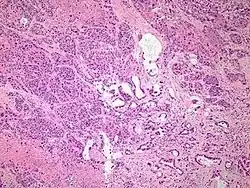

Micrograph of pancreatic ductal adenocarcinoma (the most common type of pancreatic cancer), H&E stain

The most common form of pancreatic cancer (adenocarcinoma) is typically characterized by moderately to poorly differentiated glandular structures on microscopic examination. There is typically considerable desmoplasia or formation of a dense fibrous stroma or structural tissue consisting of a range of cell types (including myofibroblasts, macrophages, lymphocytes and mast cells) and deposited material (such as type I collagen and hyaluronic acid). This creates a tumor microenvironment that is short of blood vessels (hypovascular) and so of oxygen (tumor hypoxia).[2] It is thought that this prevents many chemotherapy drugs from reaching the tumor, as one factor making the cancer especially hard to treat.[2][3]